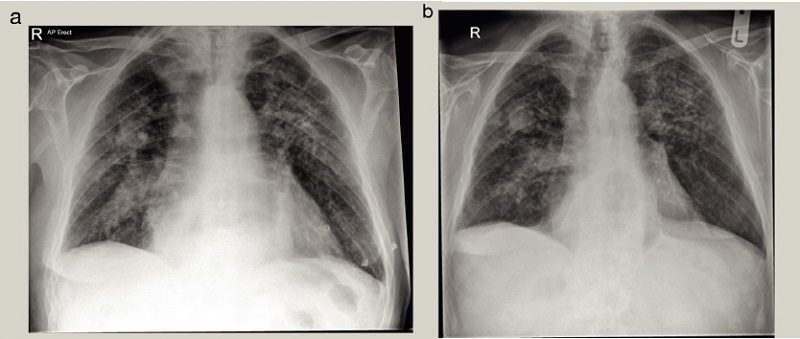

Le diagnostic de CWP simple ou compliqué repose sur des résultats radiologiques typiques et des antécédents professionnels d’exposition adéquate à la poussière de charbon. Si disponible, une radiologie préalable est particulièrement utile si elle montre des apparences relativement stables sur de nombreuses années ( Figure 1 ).

Figure 1 . Apparitions typiques à la radiographie pulmonaire d’une pneumoconiose compliquée d’un travailleur du charbon. (a) Plusieurs nodules petits et denses sont observés dans les zones supérieure et médiane, avec une opacité de 3 cm dans la zone médiane droite. (b) Les apparences radiographiques sont restées relativement stables sur une période de suivi de 4 ans.